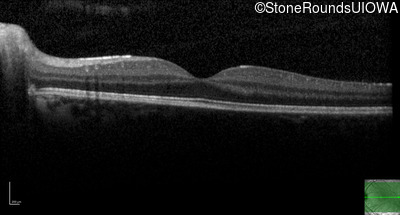

Optical Coherence Tomography - Right - 20/25 -2

Exemplar / OCT Stack